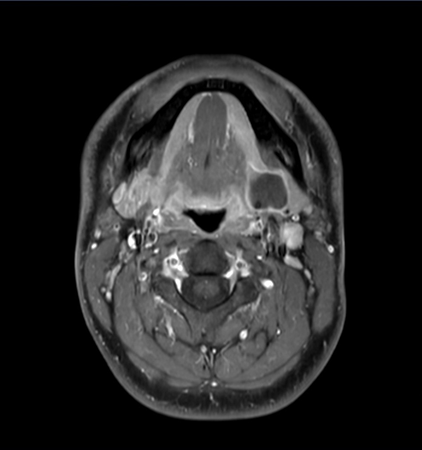

Axial mDIXON XD - T2w TSE (Water only)

Axial mDIXON XD - T1w TSE (Water only)